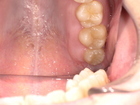

Before(抜歯前の状態)

下の歯茎へ噛み込んでいる上の親知らず(虫歯あり)

上の親知らずが過度に挺出し、下の歯茎を強く圧迫している状態でした。